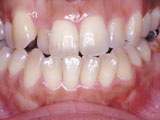

症例3:咬合(前歯が閉じない)

治療前

治療後